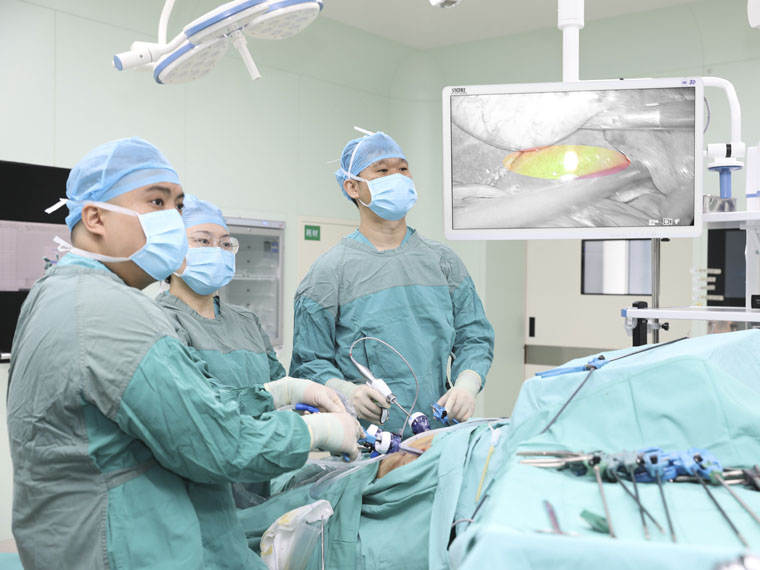

随着医疗技术的飞速发展,荧光腹腔镜技术为肝胆外科手术带来了革命性变革。近期,在彭利副院长的领导下,我院肝胆外科张萌主任医师团队联合手术室、CT磁共振科开展吲哚菁绿(ICG)荧光显影技术下的腹腔镜肝胆外科手术,该技术革新有效克服了传统腹腔镜手术中肿瘤定位困难、触觉反馈缺乏等瓶颈,显著提升了手术的精准性与安全性,为患者带来高质量的治疗效果。

肿瘤定位更精准

由于肝癌细胞对吲哚菁绿(ICG)代谢情况受损,因此通过荧光显影技术,病变细胞能够清晰呈现。这一特性不仅实现了肿瘤的精准定位,更使肿瘤边界清晰可见,帮助医生快速识别安全手术切缘,精准规划切除范围,在确保肿瘤完整切除的同时,最大限度保留健康肝组织。同时,避免误伤周围重要血管,显著提高了手术安全性,改善了患者的短期疗效和长期预后。

“隐匿”病灶无处遁形

肝癌患者多合并肝硬化背景,而腹腔镜手术因缺乏触觉反馈,致使术者在微创条件下难以识别隐匿性病灶。吲哚菁绿(ICG)荧光显影技术通过术前静脉注射造影剂,可精准定位3毫米的原发性肝癌和肝转移癌。该技术有效弥补了腹腔镜肝胆手术中触觉反馈缺失的固有缺陷,为微创精准外科提供了重要技术支撑。

荧光显影技术,可精确显示肝内隐匿病灶